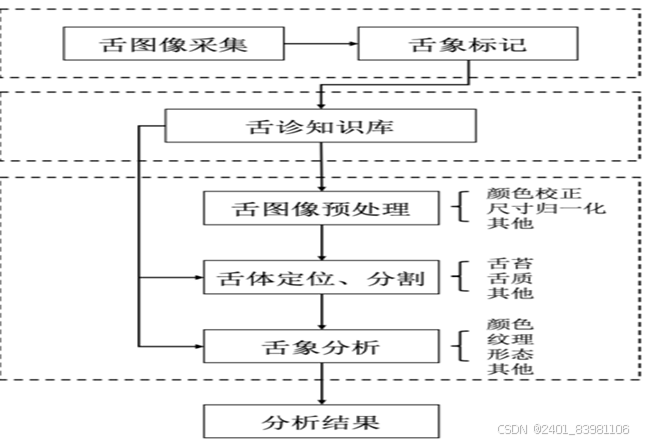

一:舌象诊断

### 舌象采集:

### 舌象分割:

一般是将舌像细分为不同的区域,使得舌像变得更加容易理解、更有意义的技术和过程,

图像分割:基于深度学习的舌头图像分割模型主要分为两类, 82 一个是U-Net83,84和 Seg-Net85,86从全卷积网络(FCN)演化而来,另一个是从CNN改进而来的Mask R-CNN, 87 广泛应用于各种类型的医学图像分割

### 舌象特征提取: